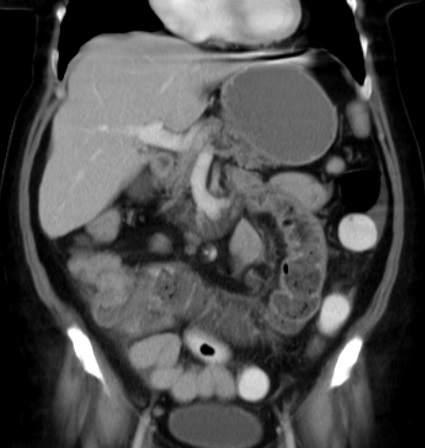

La TDM technique de tres frequemment d'utilise pour explore

des tumeur colo-rectale et les metastase . Aspect

radiologique frequemment est image de stenose irreguliere

d'une portion du colon , ou aspect stenosant en " trognon de

pomme " . Au caecum a spect radiologique parfoi est image en

laculaire ou bourgeonnante .

Image radiologique TDM et image de PET/CT des

adenocarcinomae du colon en extension localise et extension

metastasique :